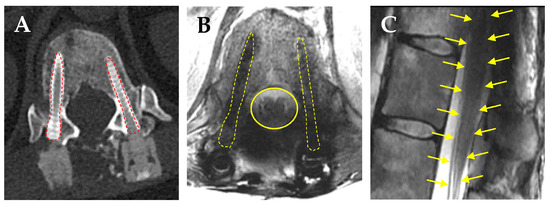

- De Almeida, R.A.A.; Ghia, A.J.; Amini, B.; Wang, C.; Alvarez-Breckenridge, C.A.; Li, J.; Rhines, L.D.; Tom, M.C.; North, R.Y.; Beckham, T.H.; et al. Quantification of MRI Artifacts in Carbon Fiber Reinforced Polyetheretherketone Thoracolumbar Pedicle Screw Constructs prior to Spinal Stereotactic Radiosurgery. Pr. Pract. Radiat. Oncol. 2024, 14, 103–111. [Google Scholar] [CrossRef] [PubMed]

- Kalasauskas, D.; Serrano, L.; Selbach, M.; Stockinger, M.; Keric, N.; Brockmann, M.A.; Ringel, F. Qualitative Assessment of Titanium versus Carbon Fiber/Polyetheretherketone Pedicle Screw-Related Artifacts: A Cadaveric Study. World Neurosurg. 2022, 166, e155–e162. [Google Scholar] [CrossRef]

- Fleege, C.; Makowski, M.; Rauschmann, M.; Fraunhoffer, K.L.; Fennema, P.; Arabmotlagh, M.; Rickert, M. Carbon fiber-reinforced pedicle screws reduce artifacts in magnetic resonance imaging of patients with lumbar spondylodesis. Sci. Rep. 2020, 10, 16094. [Google Scholar] [CrossRef]